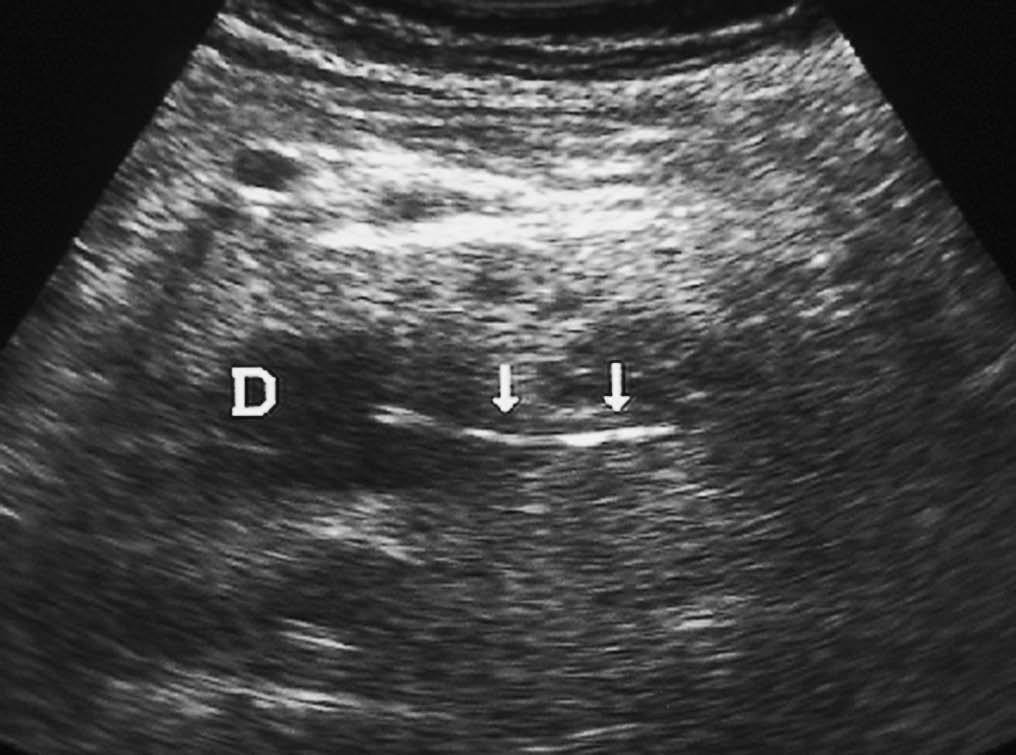

El duodeno puede lesionarse por procedimientos endoscópicos y/o quirúrgicos, al igual que por cuerpos extraños ingeridos (fig. 4). La apariencia radiológica de las lesiones será similar a las producidas por traumatismos externos, reflejando un engrosamiento de pared, alteración de la grasa periduodenal y líquido y/o aire periduodenal o en retroperitoneo en caso de rotura11.

Fig. 4--Perforación duodenal por espina de pescado. (A) Ecografía donde se observa una estructura lineal hiperecogénica (flechas) que sale del duodeno (D). (B) En el estudio de tomografía computarizada se identifica como material hiperdenso (flecha) que corresponde a la espina de pescado, con reacción de la grasa adyacente (puntas de flecha) y líquido en espacio pararrenal anterior derecho.